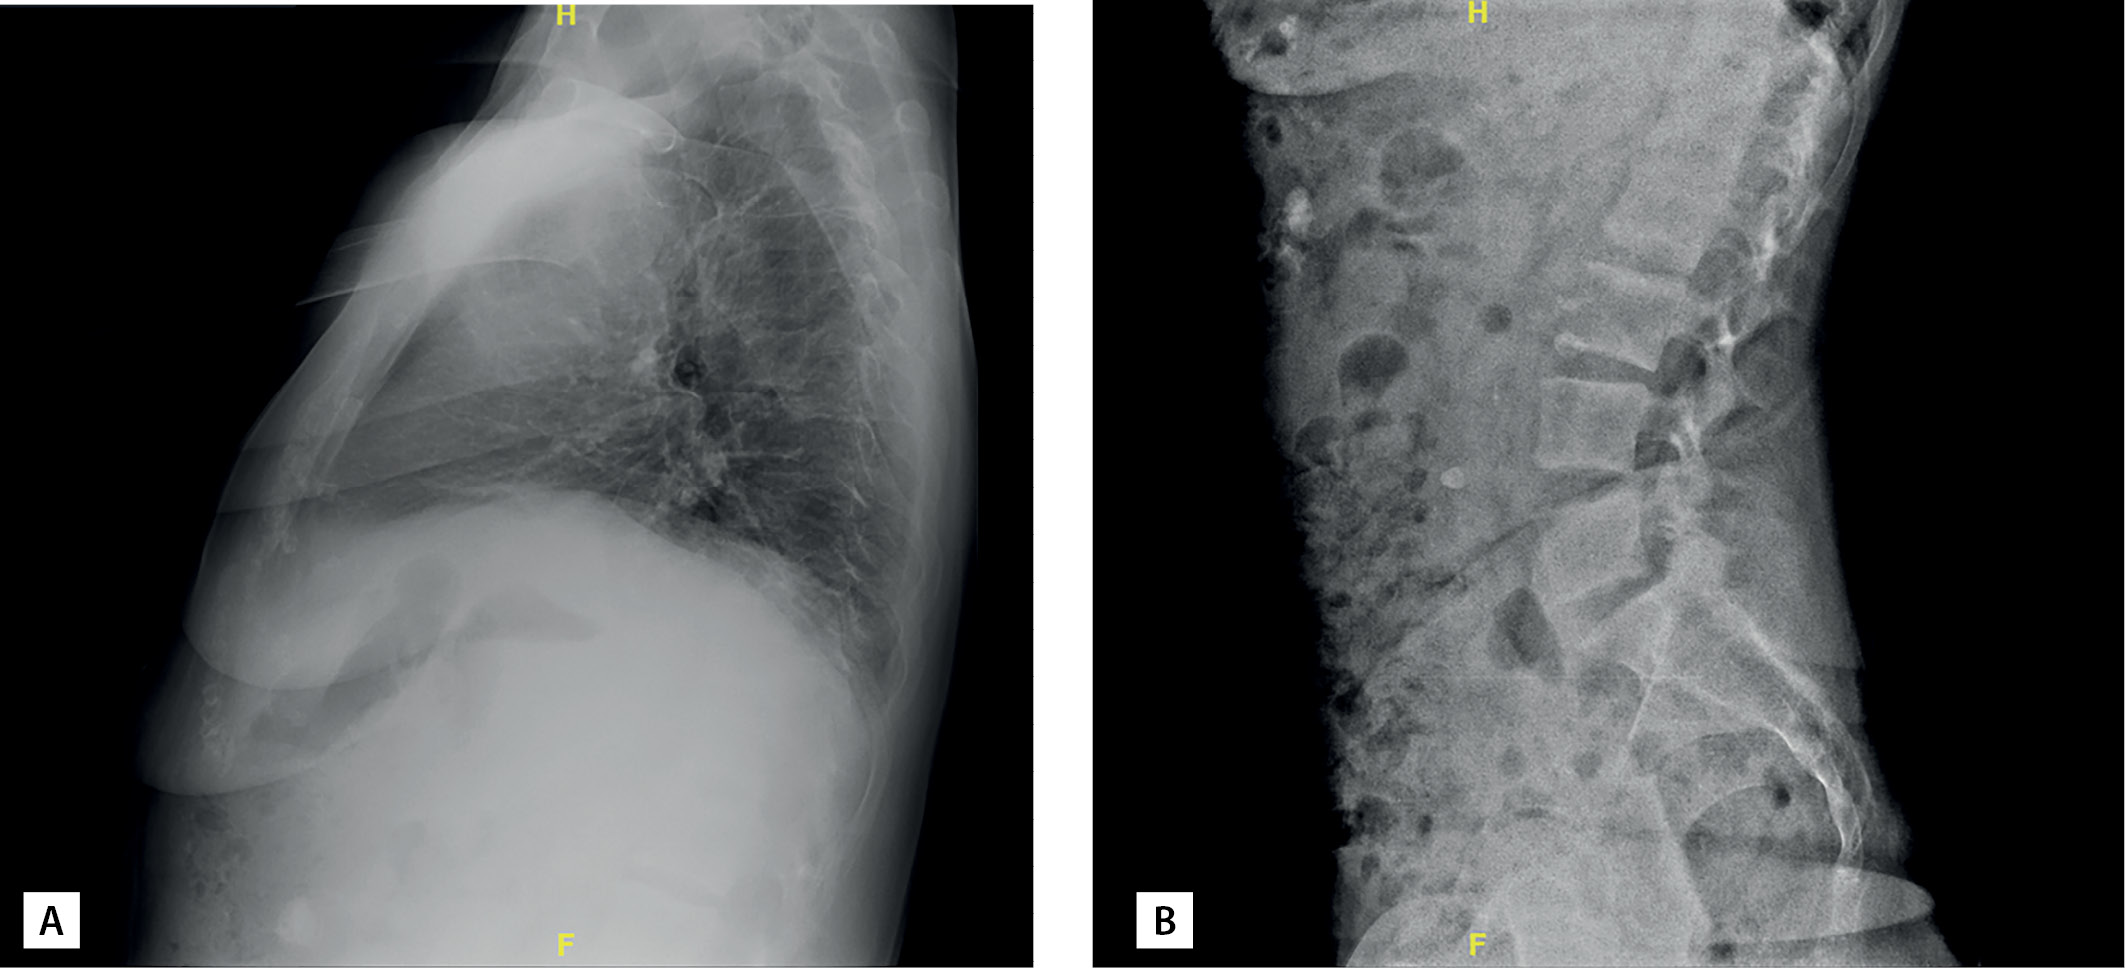

В ходе госпитализации пациентке впервые была проведена остеоденситометрия: диагностирован выраженный остеопороз поясничного отдела позвоночника и лучевой кости (табл. 2). По данным рентгенографии грудного и поясничного отделов позвоночника компрессионные переломы не определялись (рис. 1). Из дополнительных факторов риска развития остеопороза у пациентки имела место ранняя менопауза с 40 лет (заместительную гормональную терапию не получала).

Рисунок 1. Рентгенография позвоночника пациентки В.: грудного (А) и поясничного (В) отделов в боковой проекции. Пояснения в тексте.

Figure 1. X-ray of patient В’s spine: thoracic (A) and lumbar (B) sections in lateral view. Explanations in the text.

Повторная госпитализация в отделение в июне 2020 г. К ведущим жалобам при поступлении относились затруднение при самостоятельном передвижении в связи с болезненностью в правой пяточной области, выраженная общая слабость. Намомент поступления концентрация кальция в диализирующем растворе составляла 1,5 ммоль/л. По результатам рентгеновской денситометрии (через 16 мес от начала терапии терипаратидом) была отмечена значительная положительная динамика минеральной плотности кости (МПК) в поясничном отделе позвоночника и проксимальном отделе бедренной кости, умеренная отрицательная динамика в левой лучевой кости (см. табл. 2). Компрессионные переломы исключены по данным рентгенографии.